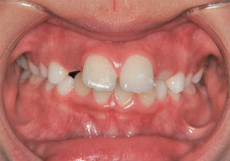

上あご前歯が前方に傾斜しており、しかも相対的に下あごが後退している上顎前突(出っ歯)の状態です。